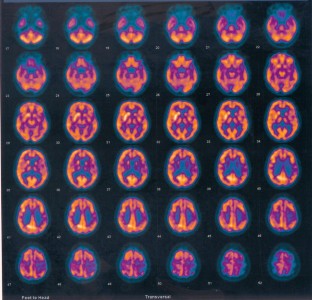

Fig. 1